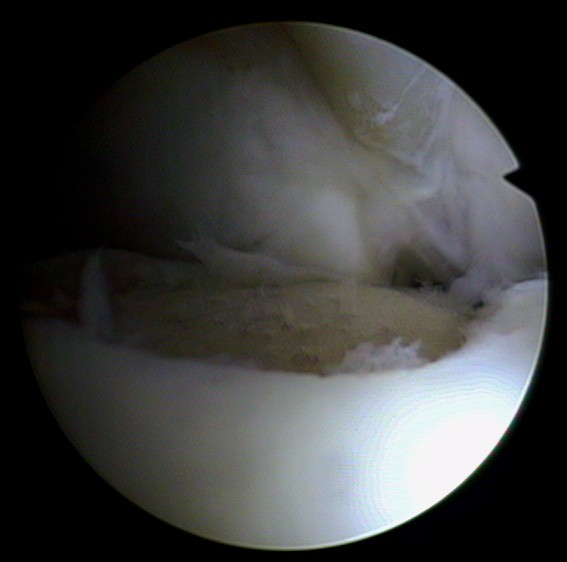

Die endoskopische Abbildung zeigt im weißen, gesunden Knorpel einen grauen Bereich mit einer Knorpelverletzung im Sprunggelenk. Unbehandelt vergrößert sich diese Knorpelverletzung. Die Läsion ist örtlich begrenzt und eignet sich für eine autologe Knorpelzelltransplantation.

Minimalinvasiv werden gesunde Knorpelzellen des Patienten gewonnen und außerhalb des Körpers im Labor vermehrt. In einem zweiten Eingriff bringt der Arzt die autologen (körpereigenen) Knorpelzellen in die geschädigte Stelle des Knorpels ein. Die Knorpelverletzung wird mit den Knorpelkügelchen bedeckt, die nach wenigen Sekunden am Untergrund haften.